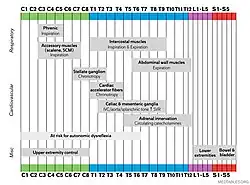

At each level of the spinal column, spinal nerves branch off from either side of the spinal cord and exit between a pair of vertebrae, to innervate a specific part of the body. The area of skin innervated by a specific spinal nerve is called a dermatome, and the group of muscles innervated by a single spinal nerve is called a myotome. The part of the spinal cord that was damaged corresponds to the spinal nerves at that level and below. Injuries can be cervical 1–8 (C1–C8), thoracic 1–12 (T1–T12), lumbar 1–5 (L1–L5),[9] or sacral (S1–S5).[10] A person's level of injury is defined as the lowest level of full sensation and function.[11] Paraplegia occurs when the legs are affected by the spinal cord damage (in thoracic, lumbar, or sacral injuries), and tetraplegia occurs when all four limbs are affected (cervical damage).[12]

Spinal cord injuries at the cervical vertebrae (neck) level result in full or partial tetraplegia, also called quadriplegia.[25] Depending on the specific location and severity of trauma, limited function may be retained. Additional symptoms of cervical injuries include low heart rate, low blood pressure, problems regulating body temperature, and breathing dysfunction.[46] If the injury is high enough in the neck to impair the muscles involved in breathing, the person may not be able to breathe without the help of an endotracheal tube and mechanical ventilator.[10]

Lumbosacral

The effects of injuries at or above the lumbar or sacral regions of the spinal cord (lower back and pelvis) include decreased control of the legs and hips, genitourinary system, and anus. People injured below level L2 may still have use of their hip flexor and knee extensor muscles.[47] Bowel and bladder function are regulated by the sacral region. It is common to experience sexual dysfunction after injury, as well as dysfunction of the bowel and bladder, including fecal and urinary incontinence.[10]

Thoracic

In addition to the problems found in lower-level injuries, thorax (chest height) spinal lesions can affect the muscles in the trunk. Injuries at the level of T1 to T8 result in inability to control the abdominal muscles. Trunk stability may be affected; even more so in higher level injuries.[48] The lower the level of injury, the less extensive its effects. Injuries from T9 to T12 result in partial loss of trunk and abdominal muscle control. Thoracic spinal injuries result in paraplegia, but function of the hands, arms, and neck are not affected.[49]

Autonomic dysreflexia

One condition that occurs typically in lesions above the T6 level is autonomic dysreflexia (AD), in which the blood pressure increases to dangerous levels, high enough to cause potentially deadly stroke.[9][50] It results from an overreaction of the system to a stimulus such as pain below the level of injury, because inhibitory signals from the brain cannot pass the lesion to dampen the excitatory sympathetic nervous system response.[6] Signs and symptoms of AD include anxiety, headache, nausea, ringing in the ears, blurred vision, flushed skin, and nasal congestion.[6] It can occur shortly after the injury or not until years later.[6]

Other autonomic functions may also be disrupted. For example, problems with body temperature regulation mostly occur in injuries at T8 and above.[47]

Neurogenic shock

Another serious complication that can result from lesions above T6 is neurogenic shock, which results from an interruption in output from the sympathetic nervous system responsible for maintaining muscle tone in the blood vessels.[6][50] Without the sympathetic input, the vessels relax and dilate.[6][50] Neurogenic shock presents with dangerously low blood pressure, low heart rate, and blood pooling in the limbs—which results in insufficient blood flow to the spinal cord and potentially further damage to it.[51]